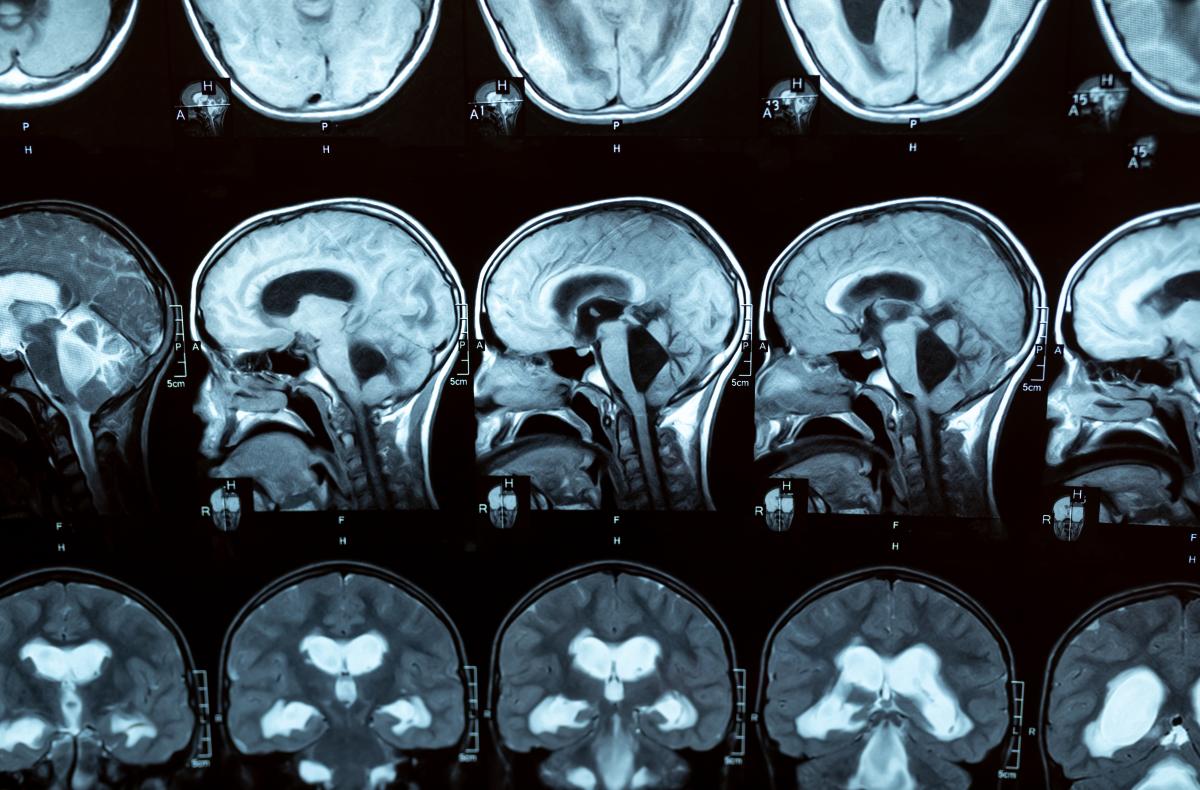

L'hydrocéphalie est une accumulation de liquide dans les cavités du cerveau (appelées ventricules), ce qui provoque leur élargissement et augmente éventuellement la pression sur le cerveau. L'hydrocéphalie est loin d'être rare dans le monde. Aux États-Unis, environ 1 bébé sur 500 naît avec une hydrocéphalie, et un plus grand nombre d'entre eux développent la maladie au cours des deux premières années de leur vie. L'hydrocéphalie n'est pas non plus l'apanage des enfants : chez les adultes, elle peut survenir à tout moment, en particulier après une infection ou une hémorragie intracrânienne, ou après l'âge de 60 ans, avec une prévalence qui augmente avec l'âge. En fait, elle est souvent sous-diagnostiquée dans cette tranche d'âge car les symptômes peuvent être attribués à la maladie d'Alzheimer ou à la maladie de Parkinson. Cela signifie évidemment que de nombreuses personnes - jusqu'à 10 % des patients atteints de démence - pourraient vivre avec une maladie traitable et non dégénérative. Imaginez ce que cela pourrait signifier en termes de qualité de vie, non seulement pour les malades, mais aussi pour leurs proches et les personnes qui s'occupent d'eux.